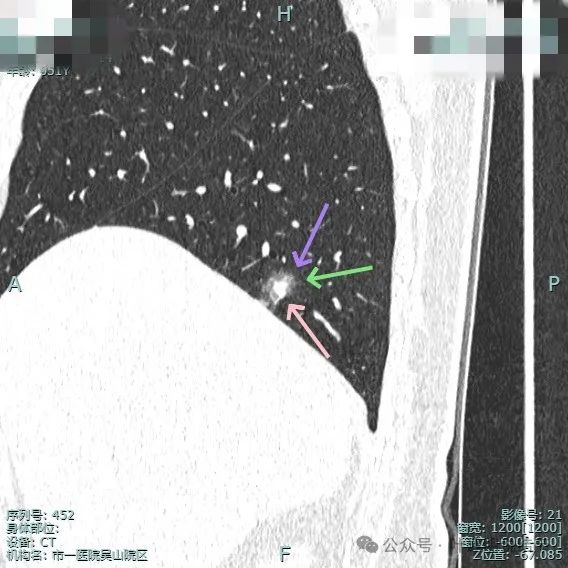

实性成分明显,但缺乏收缩力;边上是磨玻璃成分,整体轮廓较清;邻近血管走行,但没有形成血管弯征。

边缘毛糙,但瘤肺边界欠清,灶内实性成分缺乏收缩力。

磨玻璃成分有点显得像云雾状,实性成分明显,但乏收缩力。

混合密度,整体轮廓较清,瘤肺边界欠清,整体看没有收缩力。

边缘细毛刺,不太锐利;外围磨玻璃成分,瘤肺界限欠清;中间实性成分明显但缺乏收缩力,实性部分没有明显毛刺征。